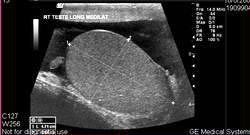

УЗИ органов мошонки - фотоУльтразвуковое исследование мошонки и ее органов не сопровождается болью и не требует специальной подготовки.